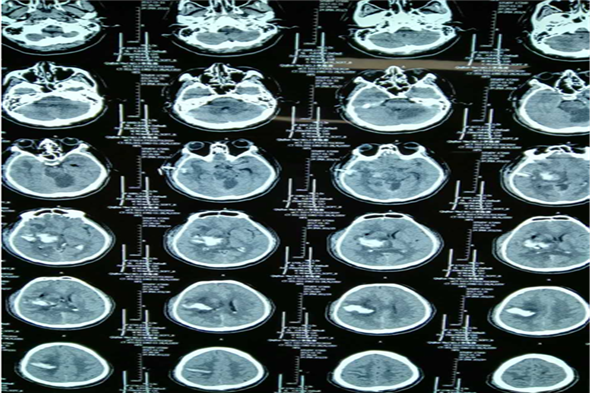

病例二 孙某,女,63岁,脑出血、脑疝。

术前脑CT

术后第三天脑CT

术后一周脑CT